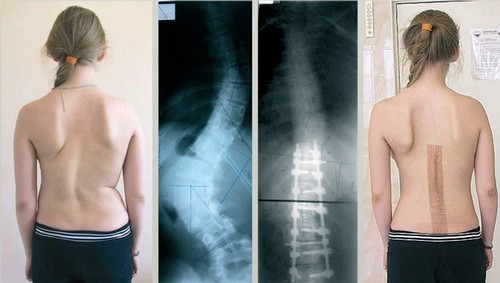

Врачи отмечают, что хирургическое лечение сколиоза является важным этапом в терапии данного заболевания, особенно в случаях, когда консервативные методы не приносят желаемых результатов. Основными показаниями для операции являются значительные углы искривления позвоночника, которые могут привести к нарушениям дыхательной функции и болевым синдромам. Среди современных методов хирургического вмешательства выделяют спинальную фузию и установку металлоконструкций, что позволяет стабилизировать позвоночник и улучшить его функциональность. Врачи подчеркивают, что выбор метода зависит от индивидуальных особенностей пациента, степени искривления и наличия сопутствующих заболеваний. После операции необходима реабилитация, которая включает физическую терапию и занятия лечебной физкультурой, что способствует восстановлению и улучшению качества жизни пациентов.

Сначала пациенту назначается тщательное обследование. Обязательным этапом является рентгенография пораженных участков позвоночника в различных проекциях. Это исследование позволяет определить степень патологических изменений и выбрать подходящий метод хирургического вмешательства.

В первые сутки после операции необходимо строго соблюдать постельный режим. Разрешены лишь минимальные движения руками и ногами. Вставать можно только через 7 дней. В этот же период проводится контрольное рентгенологическое исследование и начинаются занятия лечебной физкультурой. Массаж ног разрешен на 7–10 сутки после операции. После коррекции сколиоза 4 степени рекомендуется носить поддерживающий корсет.

Большинство операций проводятся с использованием эндоскопического метода, что минимизирует повреждения тканей. Исправление сколиоза осуществляется установкой фиксирующих устройств, которые удерживают сегменты в правильном положении и предотвращают их ненормальную подвижность. Металлические стержни могут быть подвижными или статичными. Подвижные стержни применяются для лечения сколиоза у молодежи, у которой процесс формирования скелета еще не завершен. Статичные стержни имеют более доступную цену и используются для коррекции искривления позвоночника у взрослых.